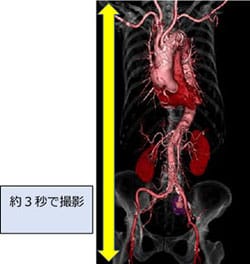

256スライスによるワイドエリア化により、全身を約3秒程度で撮影することができます。高速スキャンと高画質を両立するとともに、患者さまの息止め時間が大幅に短くなります。手術前の検査では、手術支援画像としてさまざまな3次元画像を作成することで、形態の把握や手術計画に利用しています。